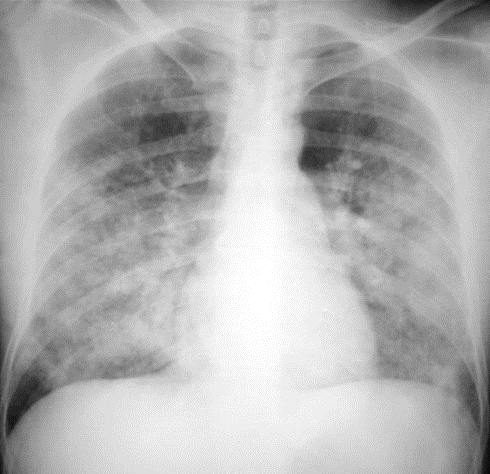

El edema agudo de pulmón es una enfermedad en la que los sacos alveolares se llenan de líquido, en la mayoría de los casos ocurre por una insuficiencia cardíaca congestiva y en otros se encuentra asociada a emergencias hipertensivas, por aumento de la presión pulmonar.

Cuando eso ocurre el paciente presenta variadas manifestaciones, como dolor de pecho acompañado de clínica respiratoria súbita y de rápida progresión, aparece hipoxemia marcada, cianosis, disnea, taquipnea, crépitos basales ascendentes. Desde el punto de vista hemodinámico el paciente presentará taquicardia y signos de shock cardiogénico en los casos en que la etiología es cardíaca y la patología entra en estadios críticos.